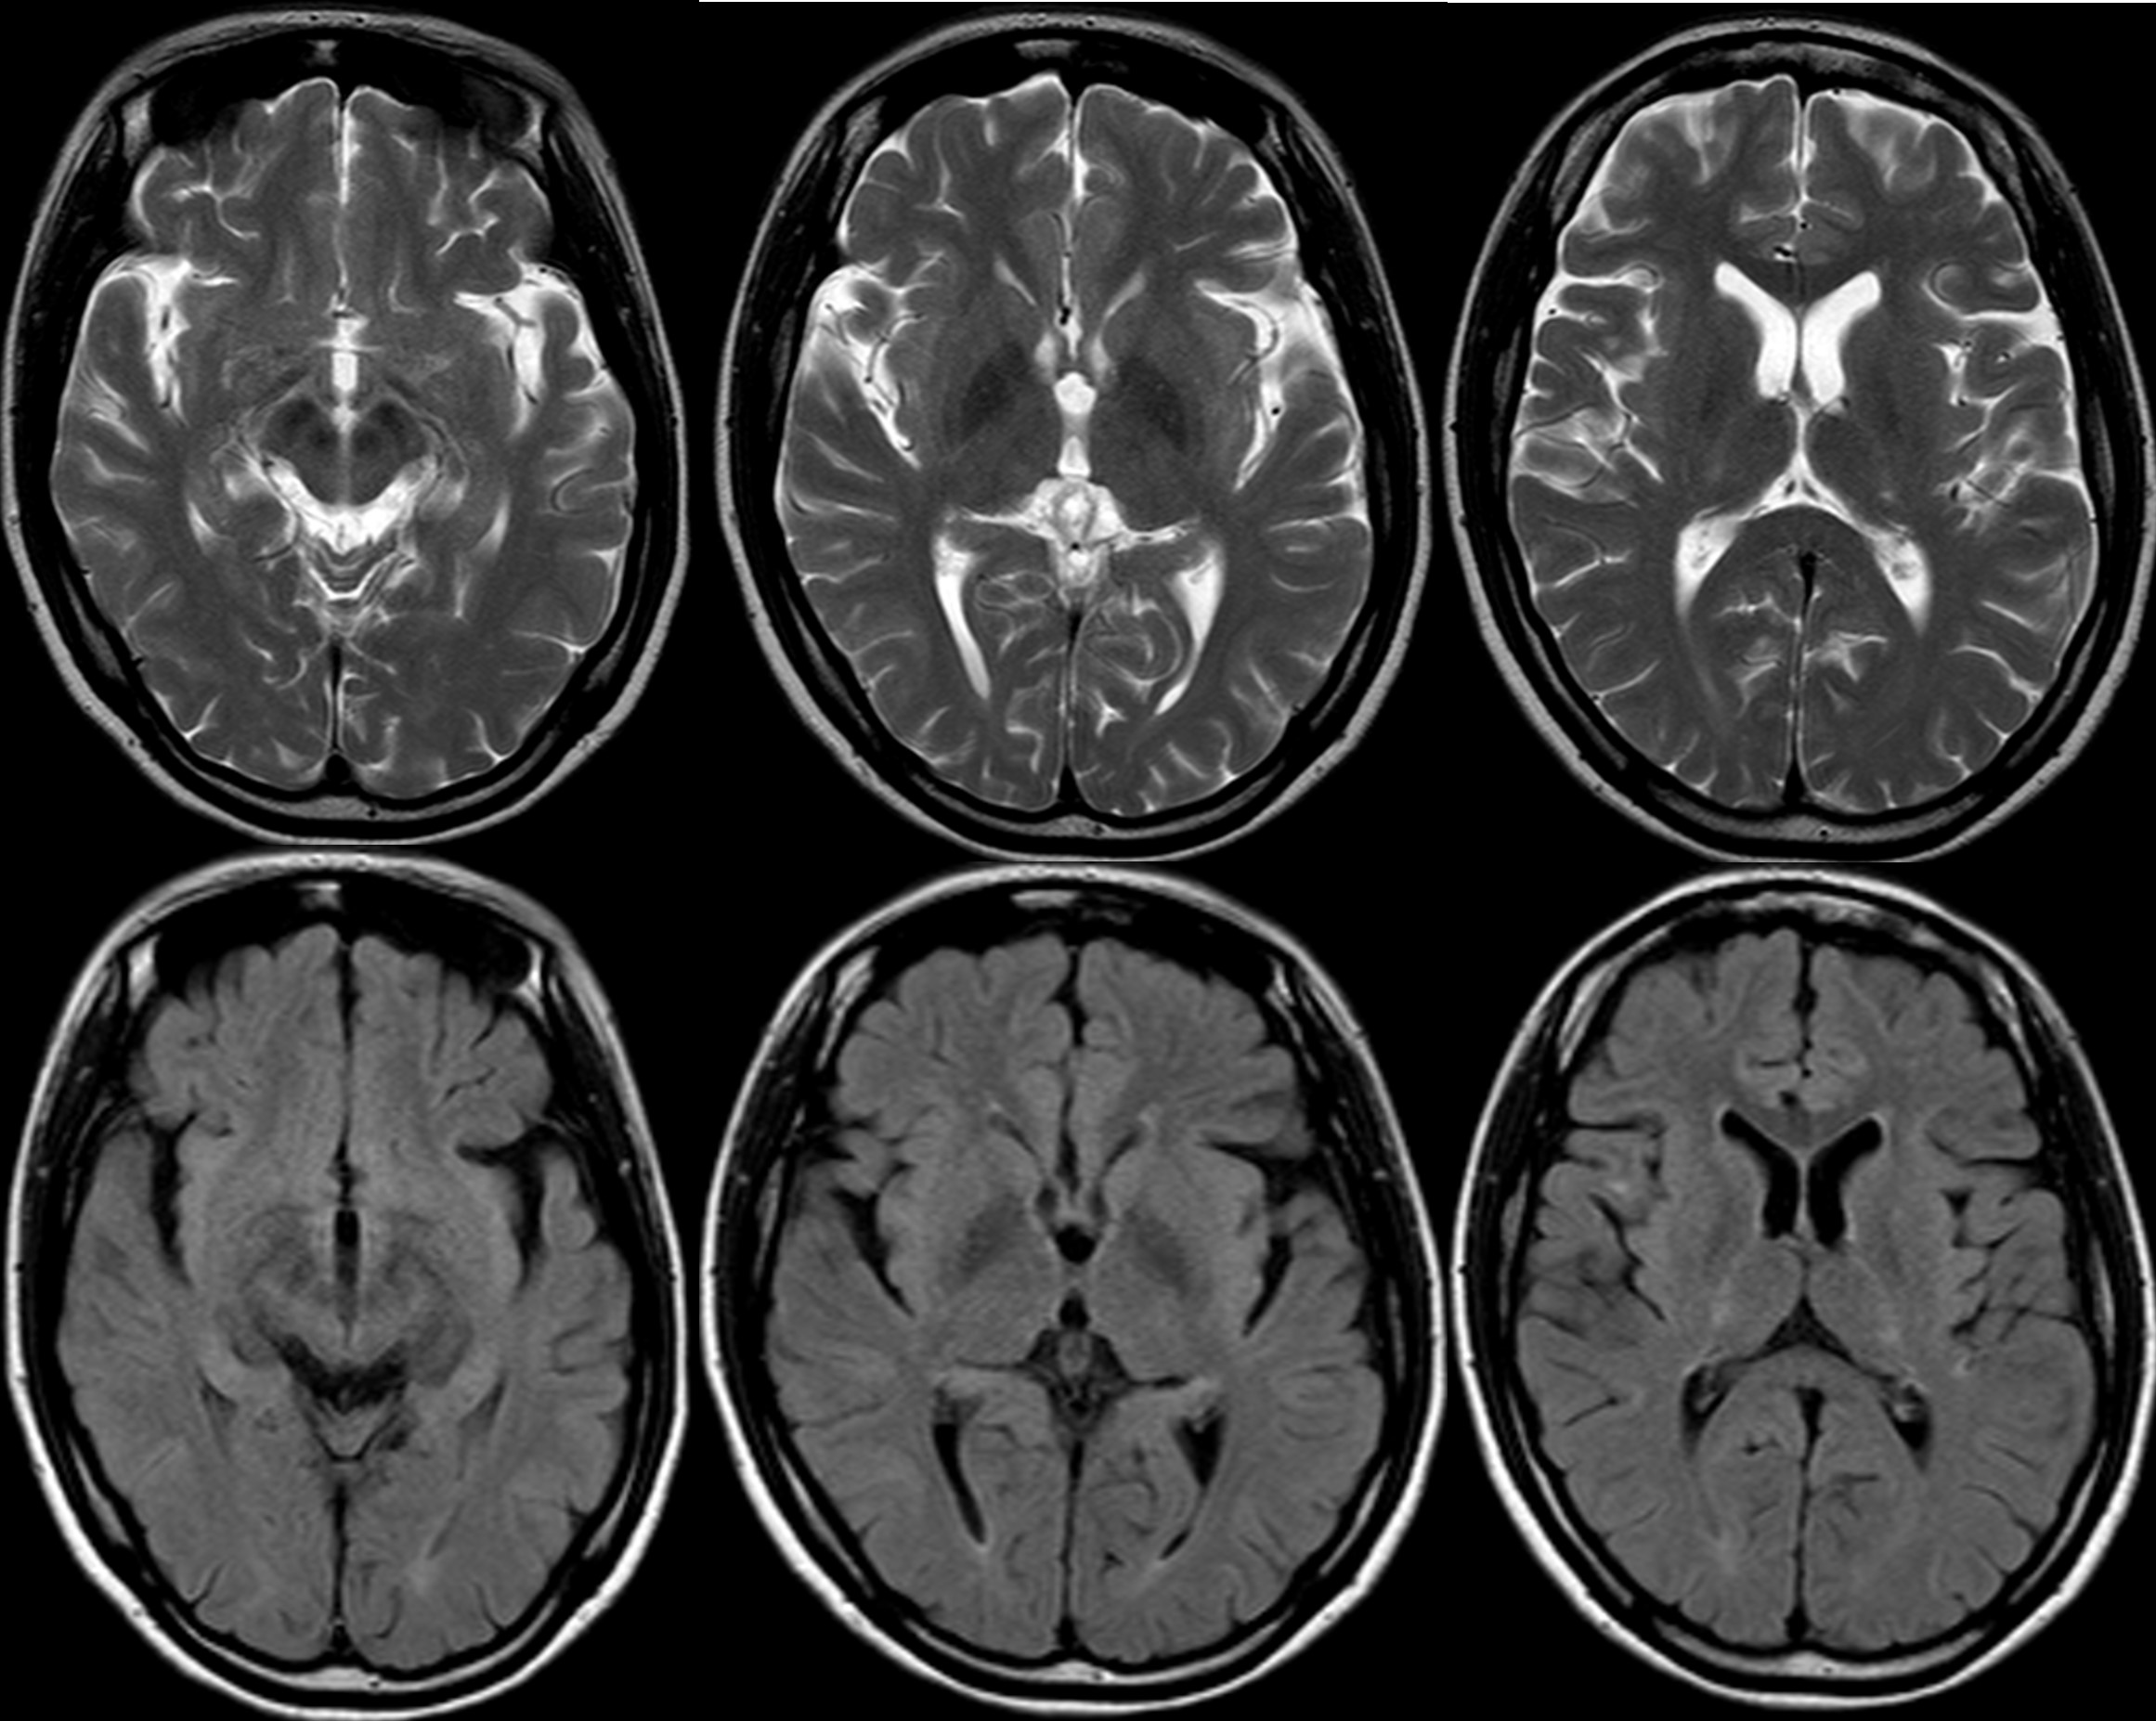

Bilateral symmetric thalamic signals in MRI

symmetric dorsal pontine signals in MRI